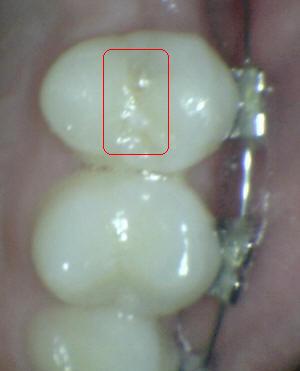

Sistema Internacional para la Detección y Evaluación de Caries (ICDAS)

¿Determine los códigos pertinentes a cada imagen?

Click en el hipervínculo: Para comparar el resultado de su diagnóstico